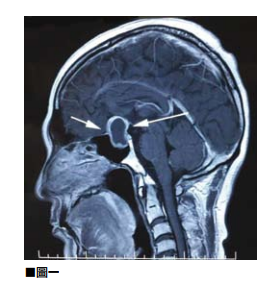

圖說01

所謂硬腦膜上出血是指,頭顱在受到撞擊後顱內血管受到創傷而流血,由於硬腦膜本身是保護腦部最外面的一層硬組織,倘若出血不是很嚴重則在傷後四至五天才會出現不尋常的劇烈頭痛。